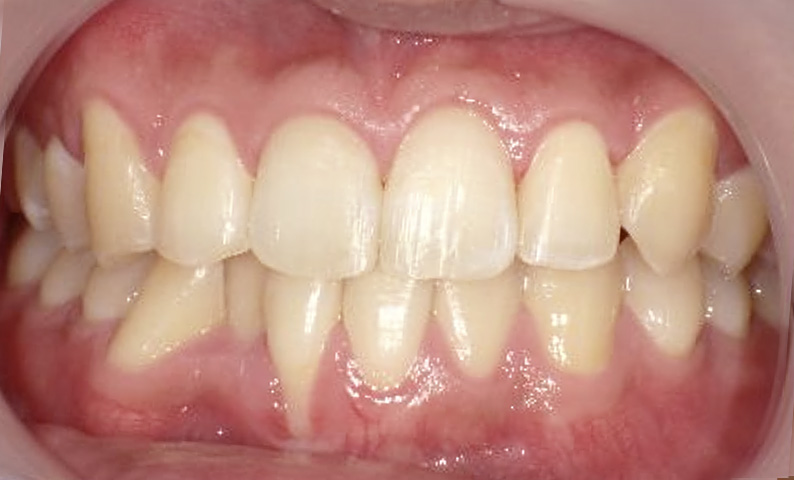

症例_025 上下顎の部分矯正

治療期間:13ヶ月金額:51万円+税女性前歯のガタガタ出っ歯

| Before | After |

|---|---|